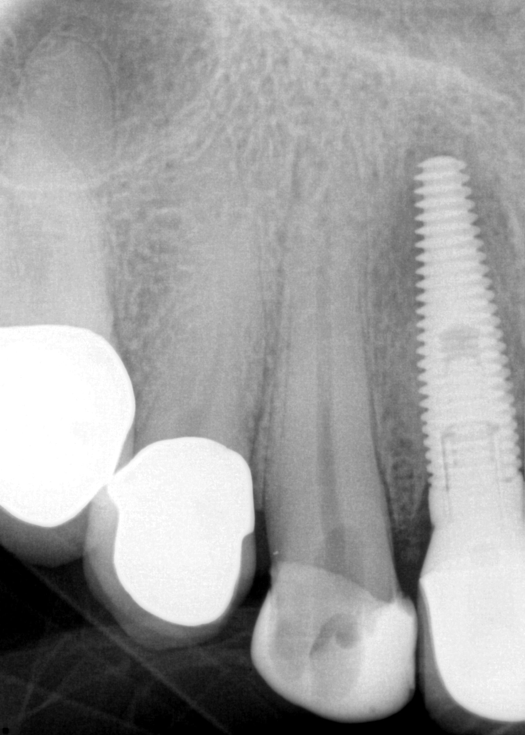

The patient returned for final evaluation of the provisional calcium-hydroxide endodontic therapy and resolution of the infection (33 days postoperatively). Fistula was not present; the tooth was not sensitive to percussion or mastication. The gold crown was removed using a high-speed metal cutting bur, the remaining caries were excavated conservatively, and the endodontic therapy was completed. Placement of glass-fiber reinforced composite and composite core buildup took place. The natural tooth structure to receive the glass-fiber post and a long-term restoration was available (Figure 8). Within one appointment, the tooth was restored (Figure 9). The patient was instructed to return for clinical and radiographic evaluation after 6 to 12 months to determine progression of periodontal healing. At that time, if the healing were adequate and the tooth were stable, evaluation of the tooth would be considered every 3 to 4 years.7

Fig 9. 33 days postoperative fiber-post placement and CAD crown.

Figure 9